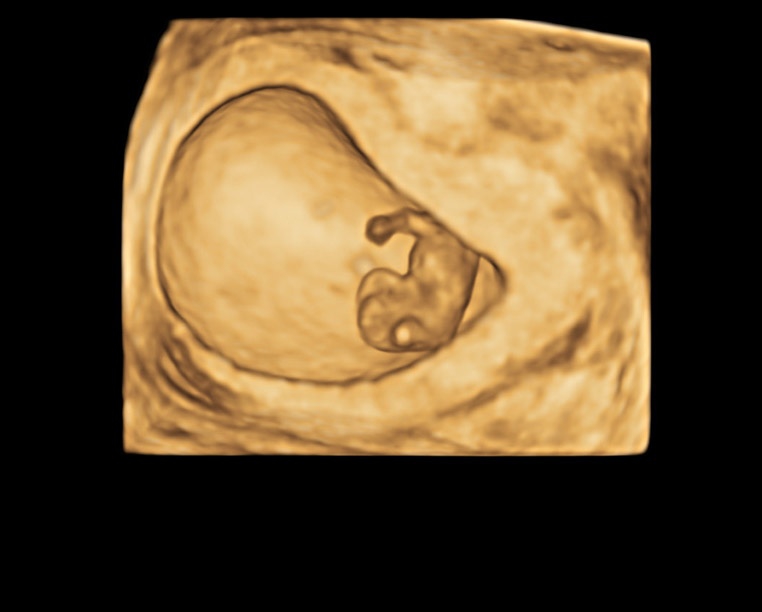

• SonoRenderlive - повышает эффективность 3D и 4D исследований путем автоматического выбора положения плоскости визуализации. Эта функция позволяет получить наиболее четкие и детальные изображения, упрощая процесс работы врача.

• Программный пакет 3D/4D Activation

• Расширенный программный пакет Advanced 3D/4D Package

• Дополнительные программные опции для объемной реконструкции 3D/4D Activation. Программный пакет 3D/4D Activation включает: режим 3D, режим 4D Realtime, SonoRenderlive – автоматическое определение границ конечностей и лица плода и получение объемного изображения в 3D/4D